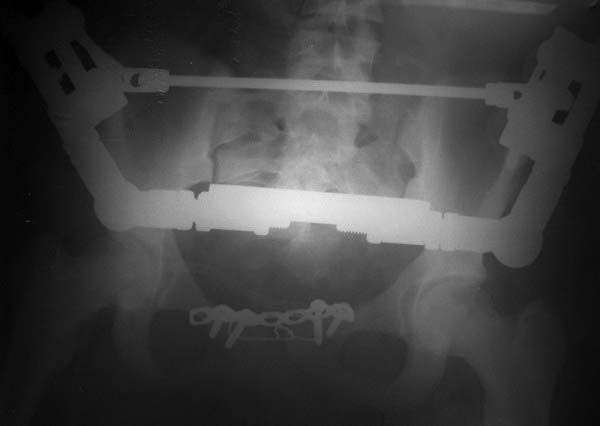

Девочка 14 лет. Кататравма (падение с высоты 4-5 этажа). Вертикально нестабильный перелом таза со смещением, разрывом лонного и левого подвздошно-крестцового сочленения, перелом крестца, открытый перелом костей голени.

Ребёнок оперирован на 10-е сутки после травмы - выполнили максимально возможную репозицию на ортопедическом столе, синтез лонного сочленения реконструктивной пластиной (из имеющихся пластин - на 7 дыр - самая длинная, получилось только по 2 шурупа с каждой стороны, поэтому пришлось подстраховаться проволокой), АВФ. Задний комплекс не фиксировали ввиду отсутствия канюлированных (да и неканюлированных)шурупов должной длинны.